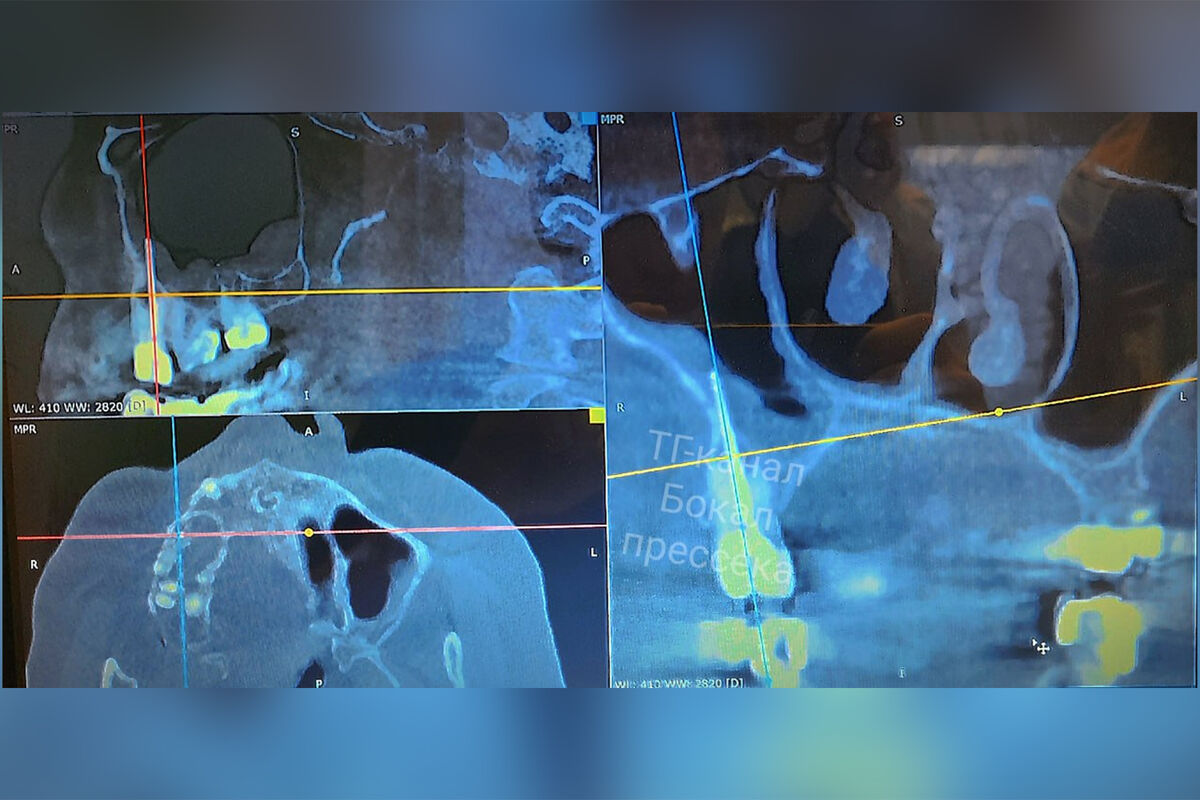

В итоге нижегородец обратился с жалобами в отделение челюстно-лицевой хирургии Нижегородской областной клинической больницы им. Н. А. Семашко. Он рассказал, что у него подозревали гайморит, но назначенная терапия облегчения не приносила. Хирурги медучреждения направили мужчину на дополнительное обследование. Во время КТ вскрылась истинная причина проблемы — боль причинял забытый отломок стоматологического инструмента. После этого часть инструмента удалили вместе с зубом, в котором он располагался.